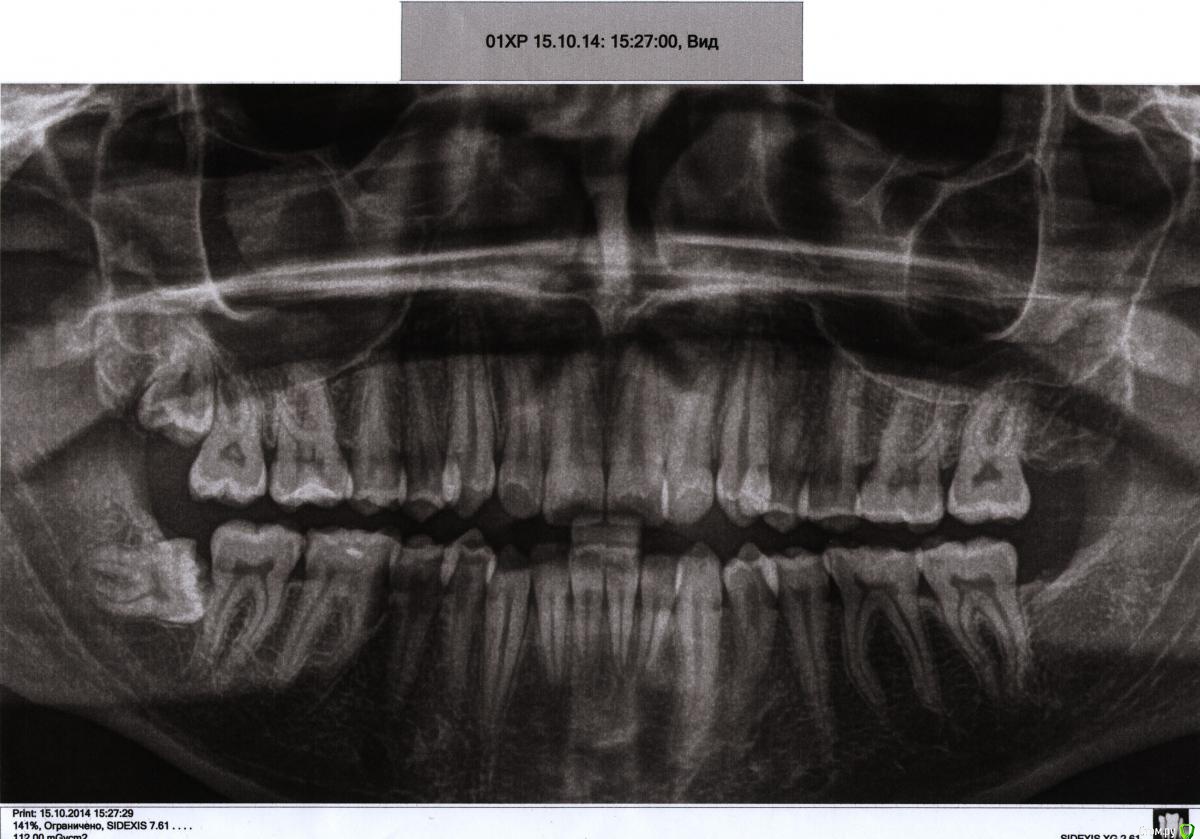

P_Aleksandrov Опубликовано 20 апреля, 2016 Поделиться Опубликовано 20 апреля, 2016 Видны ли патологии (кариес, резорбция корня, киста, гранулема и т. д.), связанные с зубами мудрости, на снимке?Возможно ли перемещение в правильное положение зубов мудрости после потери 7-х зубов? Например, может ли нижний лежачий зуб стать прямым после потери соседнего зуба? ссылки удалены администратором Ссылка на комментарий

dok1 Опубликовано 21 апреля, 2016 Поделиться Опубликовано 21 апреля, 2016 Такую мудрость нужно убирать. Могут дел натворить. Пока всё нормально. Но надолго ли..? 1 Ссылка на комментарий

IvanK Опубликовано 21 апреля, 2016 Поделиться Опубликовано 21 апреля, 2016 8ки удалятьпосмотреть с терапевтом 26,46консультация ортодонта 1 Ссылка на комментарий